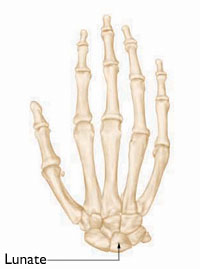

Stage 3. Both the illustration and x-ray image show that the lunate has begun to collapse and several bones in the wrist have shifted out of position.

Reproduced and adapted with permission from Allan CH, Joshi A, Lichtman DM: Kienböck's disease: diagnosis and treatment. J Am Acad Orthop Surg 2001; 9 : 128-136.

Stage 4. (Left) This illustration shows damage to several bones in the wrist. (Right) This CT scan also shows deterioration in the bones of the wrist.